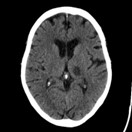

History of Ischemic Stroke

2 years ago. Diagnosed as a left middle cerebral artery (MCA) lacunar infarct.

• Sequelae: Mild, persistent weakness in his left leg. He walks with a slight limp but is fully independent and ambulatory, with no residual arm or speech deficits.

• Previous CT-scan: